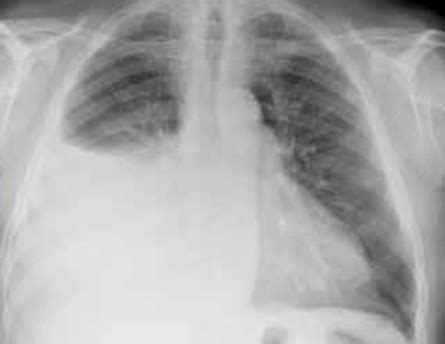

Le indagini di imaging toracico hanno rivelato infiltrati alveolo-interstiziali bilaterali diffusi e un'effusione pleurica bilaterale. Le estese indagini microbiologiche e autoimmuni sono risultate negative, escludendo altre cause comuni. L'eosinofilia è stata identificata nel lavaggio broncoalveolare (BAL) e nella citologia del liquido pleurico, suggerendo la diagnosi di AEP.

- Imaging: Radiografia del torace e, se necessario, TC torace per valutare l'estensione degli infiltrati polmonari e l'effusione pleurica.